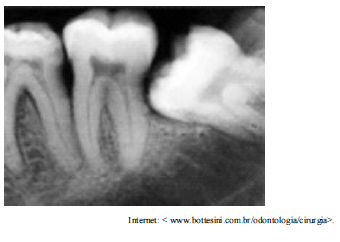

Um paciente do sexo masculino, de vinte e cinco anos de idade, procurou atendimento odontológico queixando-se de dor, gosto desagradável e inchaço na gengiva, na região do segundo molar inferior esquerdo. O paciente relatou, ainda, que apresentou um pouco de dificuldade na ingestão, além de febre e mal-estar nos dois últimos dias. No exame clínico, o paciente apresentou trismo leve, linfoadenopatia e halitose. A imagem apresentada mostra o resultado da radiografia realizada no paciente.

Com relação a esse caso clínico, julgue os itens que se seguem, considerando a imagem radiográfica apresentada.